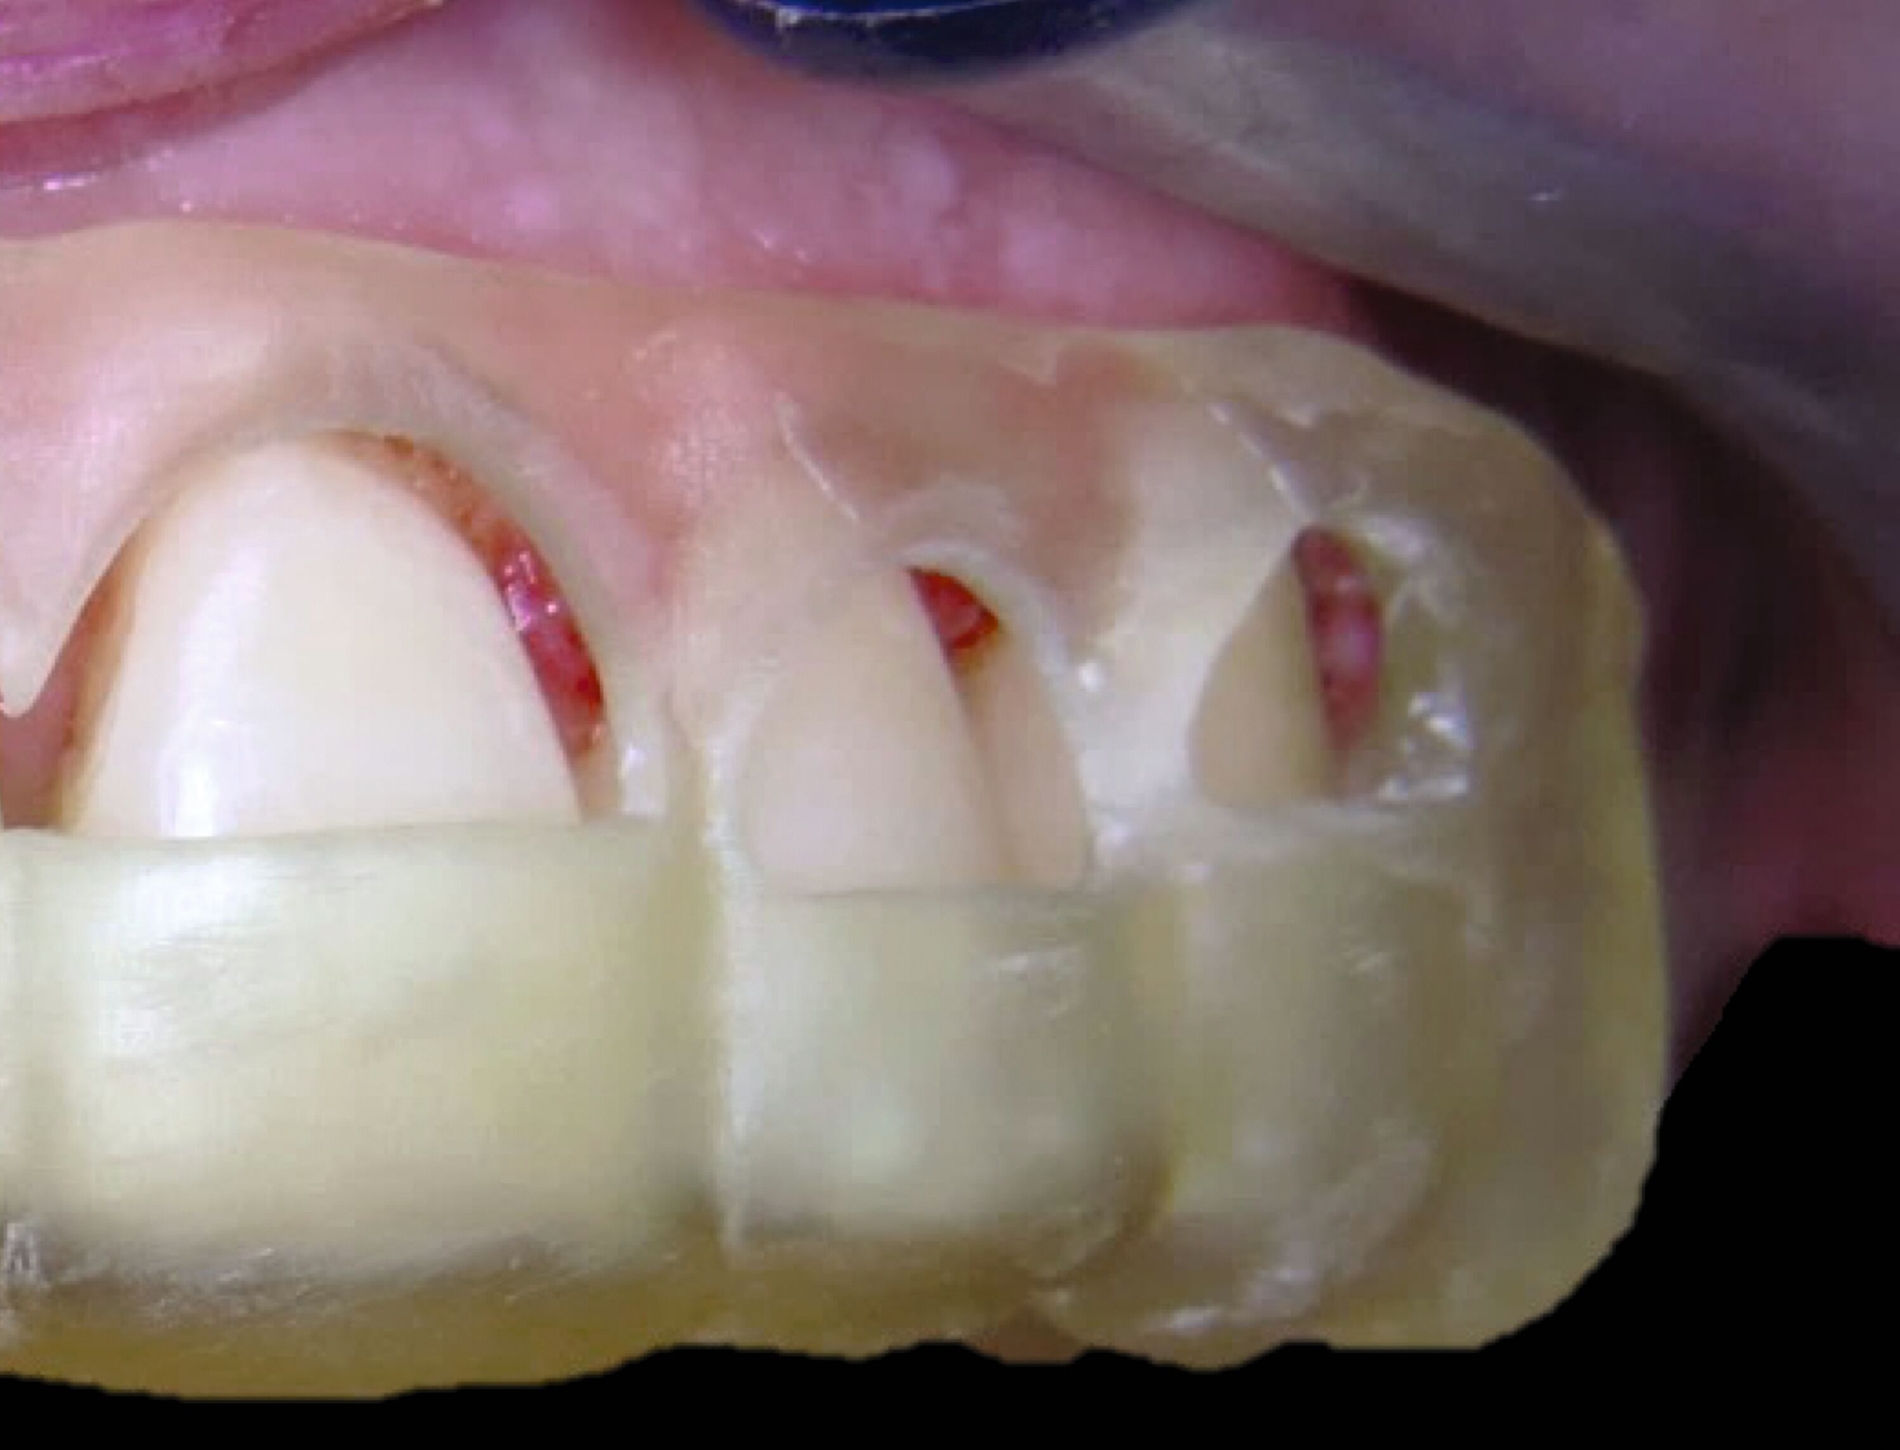

Unter den digital gefertigten kieferorthopädischen Apparaturen sind Aligner wohl das bekannteste Beispiel [Ercoli et al., 2014, Robertson et al., 2020]. Die Herstellung von Alignern selbst basiert(e) jedoch auf einer manuellen Fertigung anhand 3-D-gedruckter Modelle und stellt(e) somit bisher eher eine partiell automatisierte Fertigung dar. Die neuesten Entwicklungen erlauben mittlerweile eine Fertigung im direkten 3-D-Druckverfahren [Tartaglia et al., 2021], so dass mühsame, zeitaufwendige Zwischenschritte der manuellen Fertigung entfallen (Abbildung 1a). Weiter profitieren die Patienten von individuelleren Fertigungsmöglichkeiten, da durch die Umsetzung im 3-D-Druck zusätzliche Elemente einfacher und stabiler in den Aligner inkorporiert werden können (Abbildung 1b).

Auch die Herstellung zusätzlicher Elemente, wie beispielsweise Transpalatinalbögen aus Keramik-gefüllten 3-D-Druckkunststoffen, ist möglich (Abbildung 2c) [Thurzo et al., 2022], muss jedoch in großangelegten Studien noch auf eine ausreichende klinische Suffizienz untersucht werden. Weiter bieten 3-D-gedruckte Transferguides die Möglichkeit des „Indirekten Klebens“ [Deahl et al., 2007; Bozelli et al., 2013; Li et al., 2019; Sabbagh et al., 2022], wobei die Bracketpositionierung bereits vor dem Einsatz digital festgelegt und schließlich durch den Transferguide intraoral übertragen wird (Abbildung 2d). Neben einer verkürzten Stuhlzeit erlaubt dieses Verfahren eine besonders hohe Genauigkeit der Bracketpositionierung.